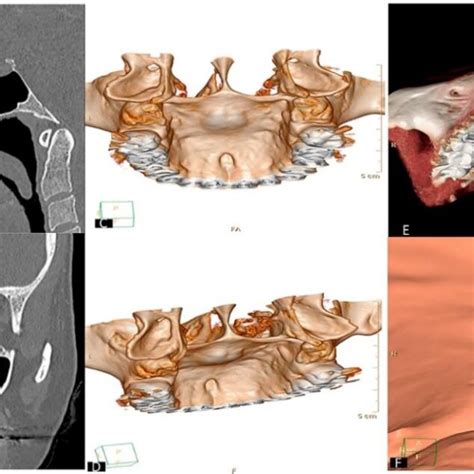

- Dientes supernumerarios (hiperdoncia): aunque suene extraño, a veces un “bulto” duro en el paladar puede ser en realidad un diente de más que está erupcionando en un lugar inusual. Por ejemplo, existen casos de incisivos extra (mesiodens) que aparecen en el paladar detrás de los dos frontales, o de muelas adicionales. Estos dientes extras pueden sentirse como protuberancias óseas.